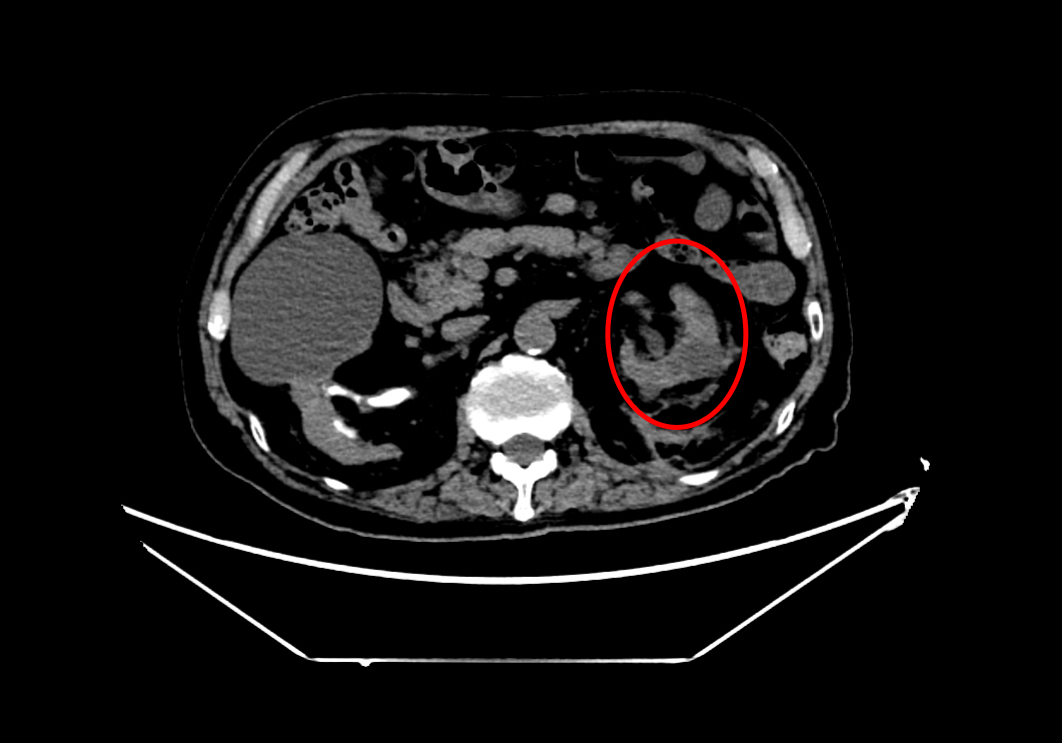

术后左侧输尿管

术后左肾

手术团队凭借丰富经验与精湛技术,精准建立经皮肾通道,顺利实施钬激光碎石取石及输尿管支架置入。术中患者出血少,生命体征平稳,手术圆满完成。